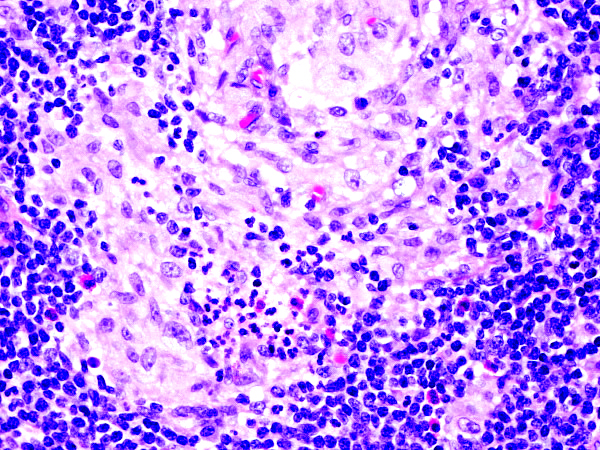

Microscopic (histologic) description

- Early: tiny necrotic foci with neutrophils

- Late: stellate abscesses surrounded by pale epithelioid cells

- Abscesses may merge and sinus tracts may develop

- Macrophages may have organisms within vacuoles

Microscopic (histologic) images

Contributed by Mark R. Wick, M.D.